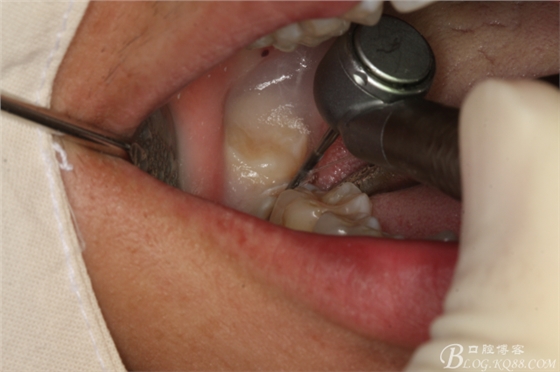

圖8.先橫斷47牙冠,盡量從牙頸部橫斷

圖9.潛掘法橫斷牙冠